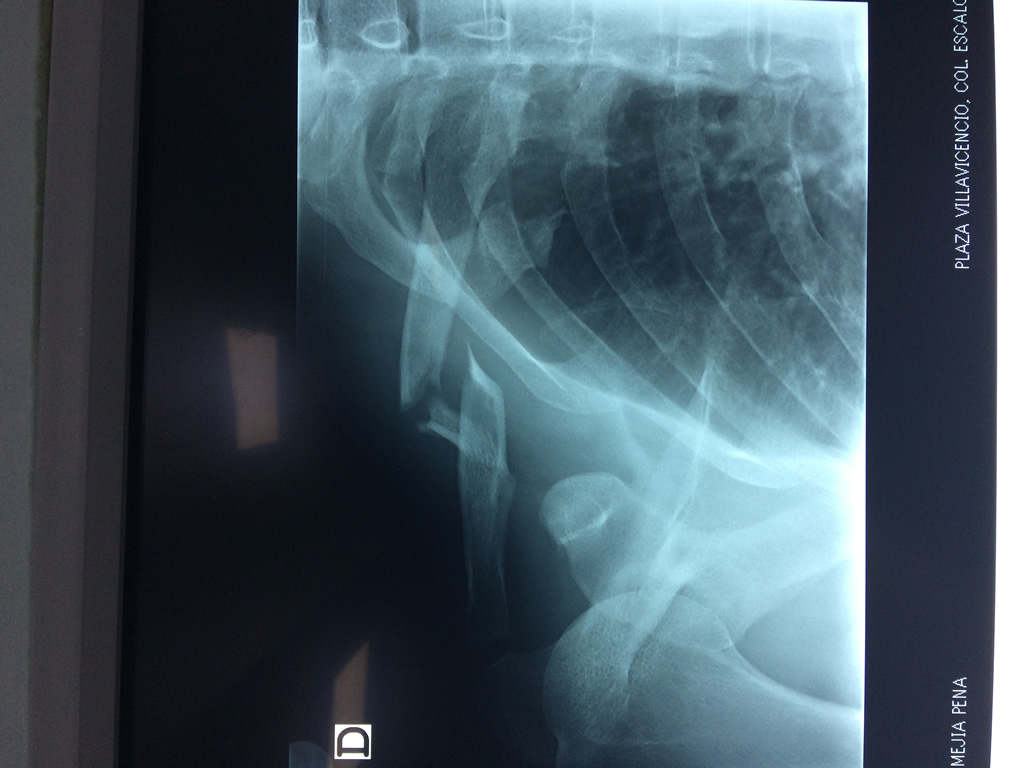

Clavícula

La clavícula es un hueso largo, con forma de "S" itálica, situado en la parte anterosuperior del tórax. Junto con la escápula forman la cintura escapular. Se puede palpar por toda su longitud y se extiende del esternón al acromion de la escápula, siguiendo una dirección oblicua lateral y posterior.

Se considera el único medio de unión entre el miembro superior y el tórax. A pesar de su aspecto, similar al de un hueso largo, posee una estructura semejante a la de un hueso plano, ya que carece de epífisis y de diáfisis, lo que la harían entrar dentro de la clasificación de hueso largo. Carece de un canal medular propiamente dicho.